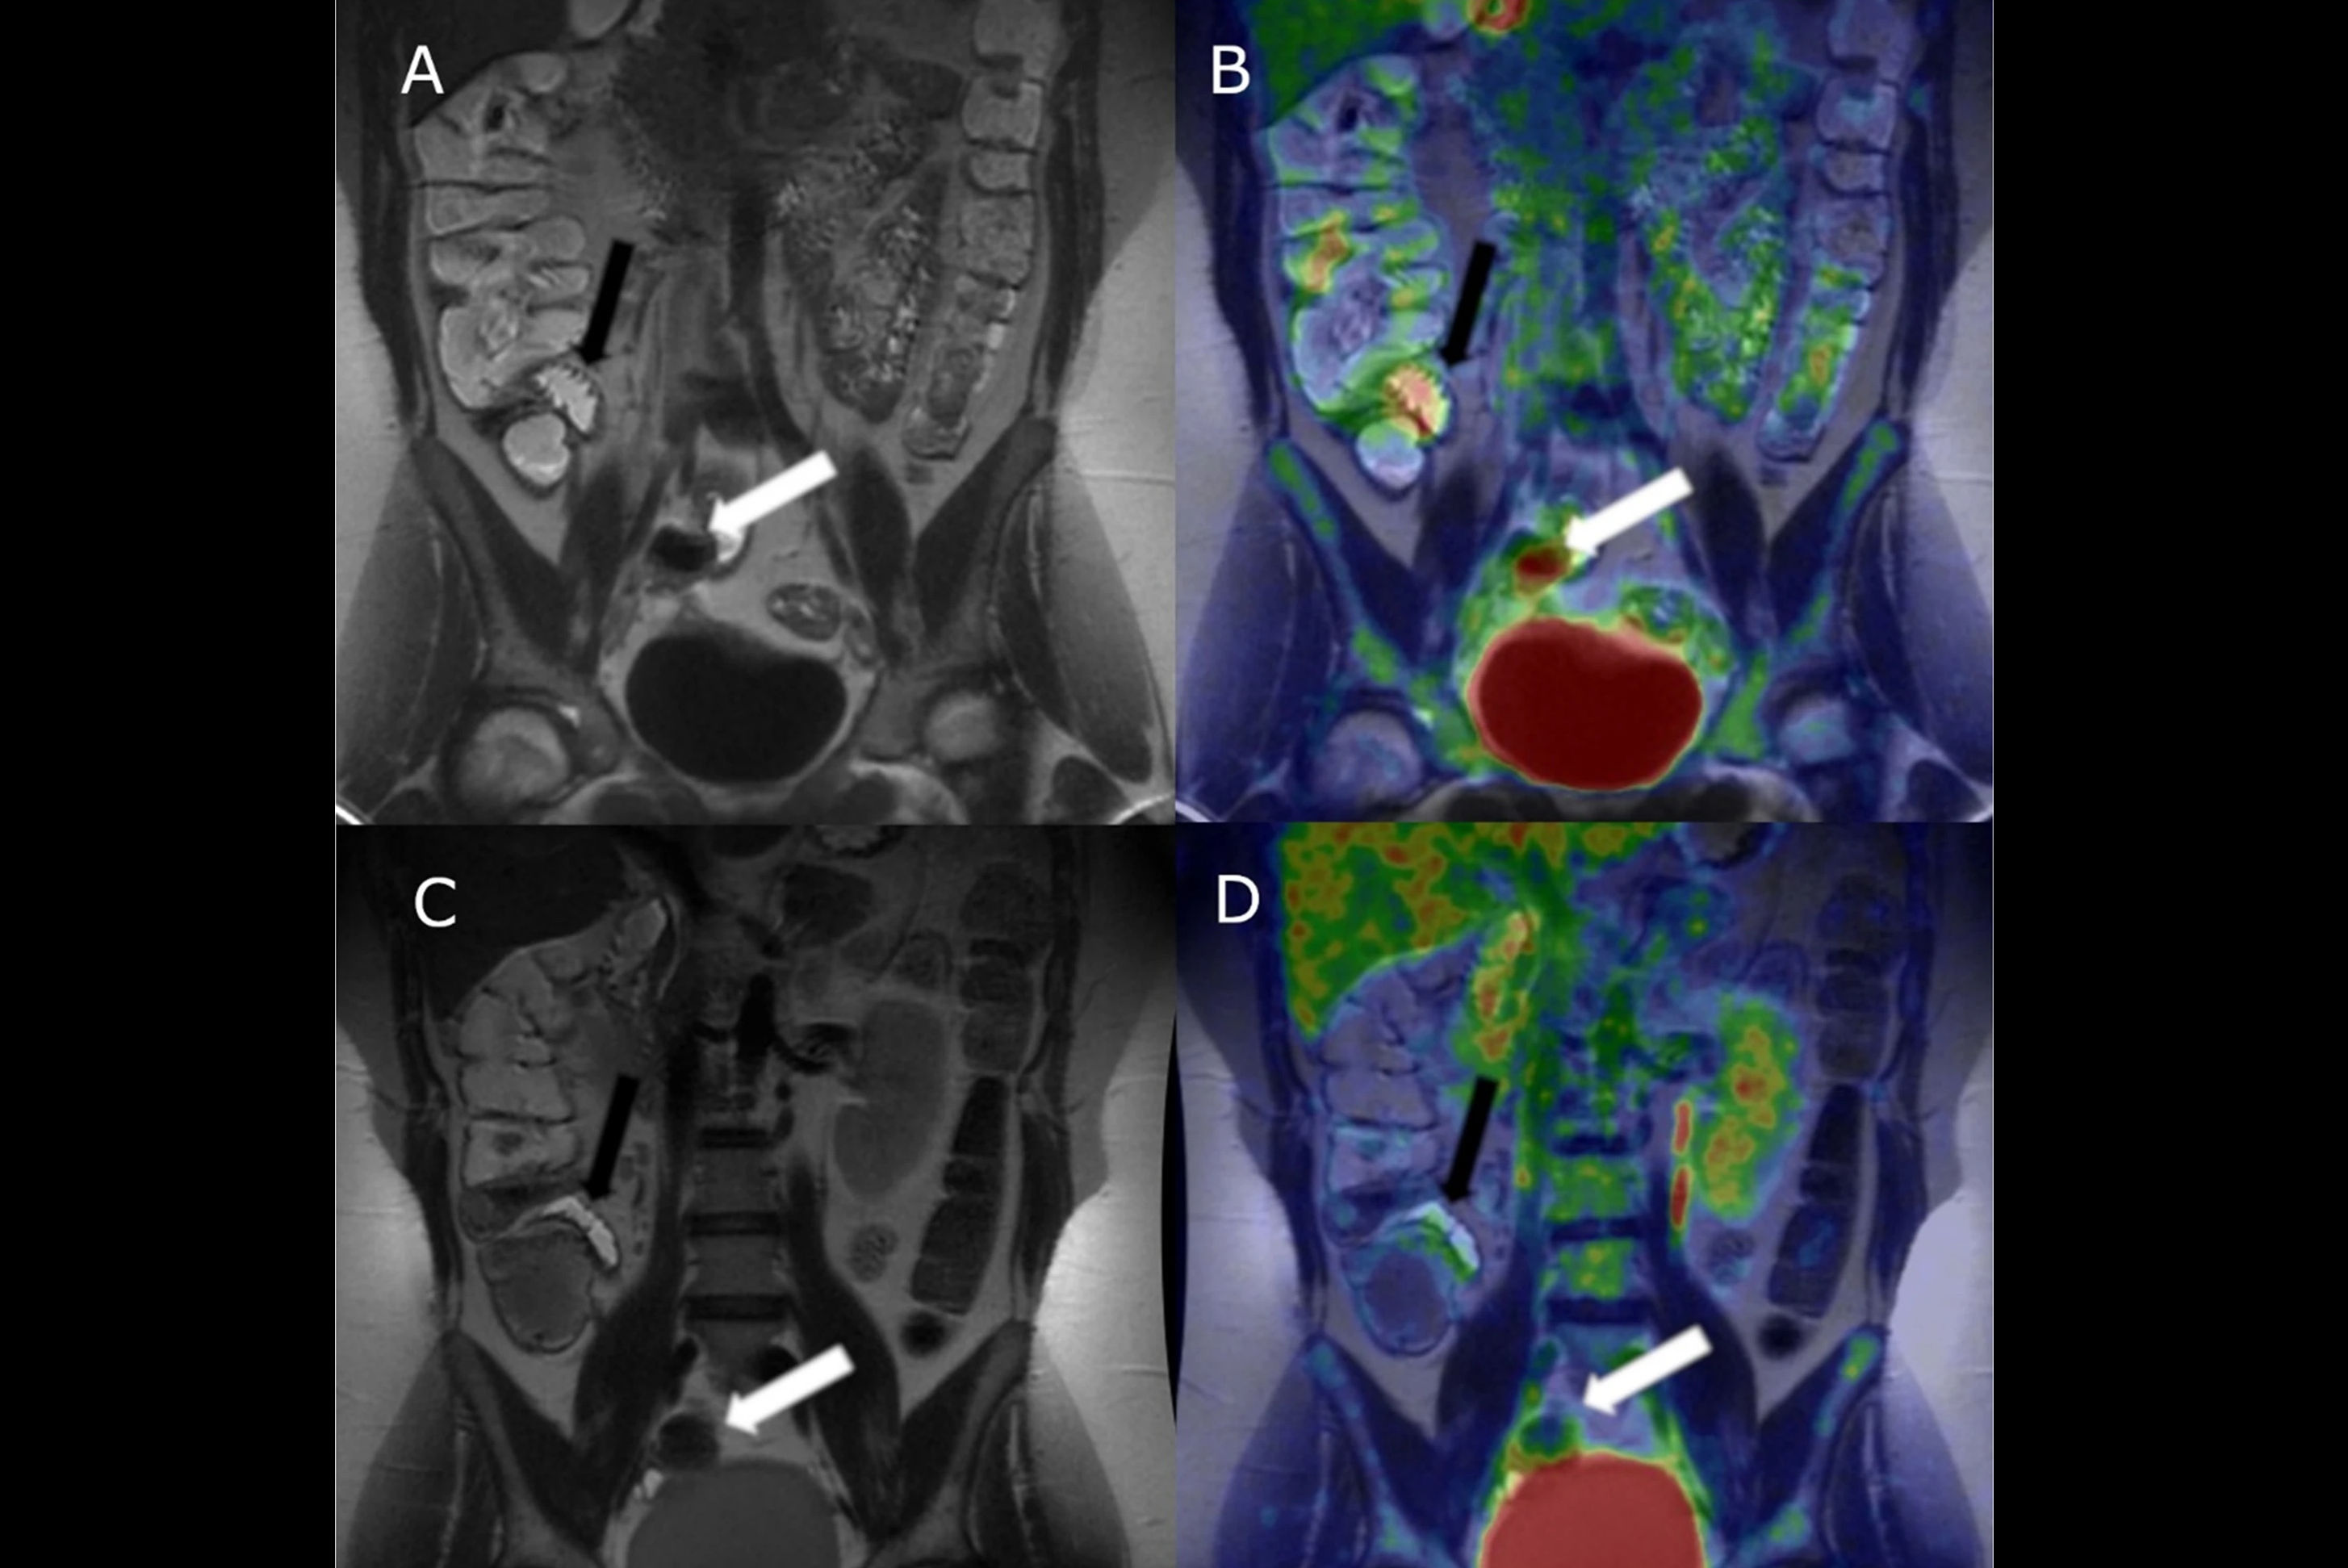

Coronal single-shot fast spin-echo and postgadolinium images demonstrate the proximal, mid, and distal aspects of a naive stricture at MR enterography performed in a 71-year-old female patient. There is a long inflammatory stricture with multifocal areas of luminal narrowing and intervening areas of active inflammation involving the terminal ileum. The four central readers measured this stricture as being 70.1 cm, 69.8 cm, 71.7 cm, and 71.6 cm in length … The arrows point to a single stricture that was assessed by all readers. Colored dots in the left-most and right-most images are reader markings along the lumen of the stricture. Postgadolinium images are the middle images. Images and caption courtesy of the RSNA.